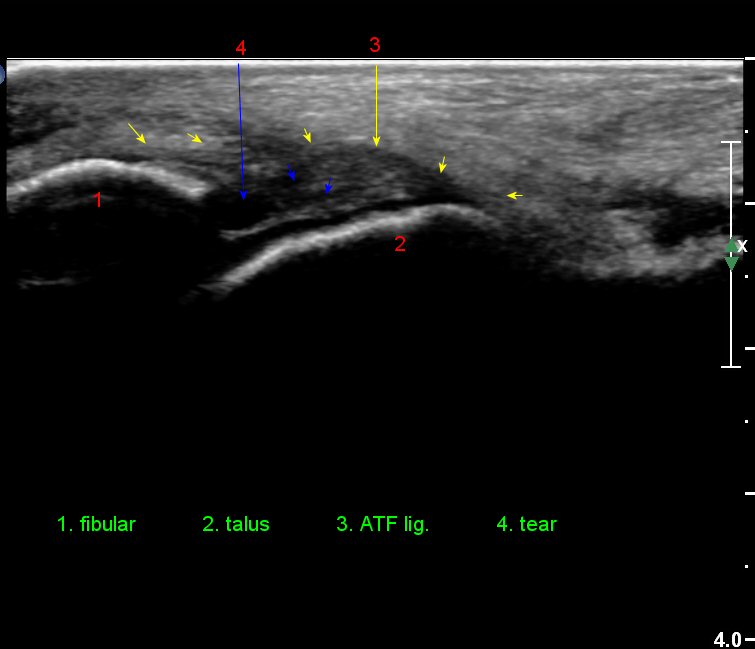

¹ß¸ñ°üÀý ¾ÕÂÊ Á¾´Ü¸é°Ë»ç¿¡¼­ ƯÀÌ ¼Ò°ßÀ» º¸ÀÌÁö ¾ÊÀ¸³ª(»çÁø 1)

Àü°ÅºñÀδë Á¾´Ü¸é°Ë»ç¿¡¼­ ¾È´ë ºñ°ñ ºÎÂøºÎÀÇ Àú¿¡ÄÚ ºÎÁ¾°ú ºÎºÐÆÄ¿­ÀÌ °üÂûµÈ´Ù(»çÁø 4).

°ÇÃø°ú ºñ±³Çϸé È¯ÃøÀÇ º´Àû ¼Ò°ßÀÌ ¶Ñ·ÈÇÏ´Ù(»çÁø 7).

Àü°ÅºñÀδë Á¾´Ü¸é°Ë»ç¿¡¼­  Àú¿¡ÄÚ ºÎÁ¾ÀÌ °¨¼ÒÇϰí ÀδëÀÇ ¿¡ÄÚ°¡ Áõ°¡µÇ¾ú´Ù(»çÁø 2, 3, 4).